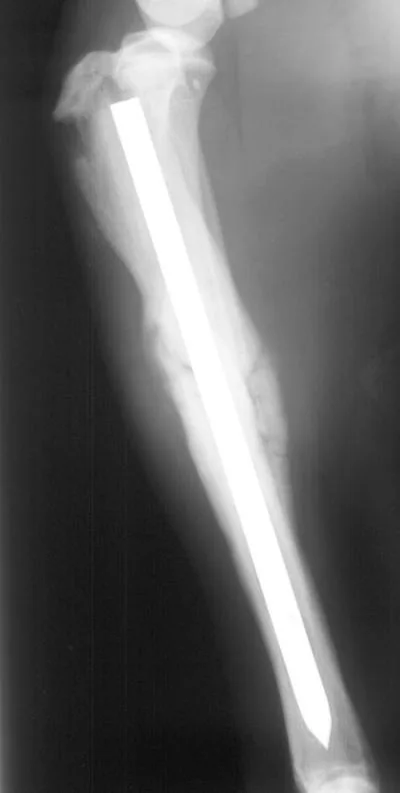

Fractures managed using interlocking nails and biologic technique develop extensive bridging callus and early return to function. A minimally invasive surgical approach (note the surgical skin staples) was made to this fracture to minimize disruption of the blood supply to the bone fragment. The fracture fragments quickly become incorporated in the callus if soft tissue attachments can be maintained.

Healing of the comminuted tibial fracture shown in Figures 2A and 2B after stabilization using an interlocking nail system. This fracture reached bony union in 8 weeks.